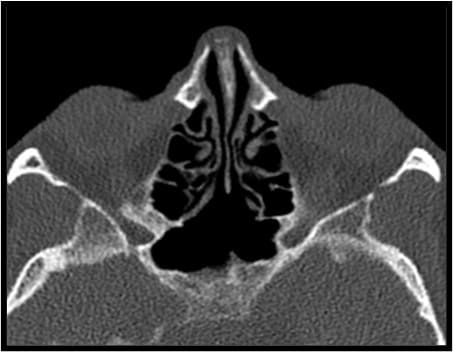

Figure 3: (A) Coronal cadaver view of the sphenoid sinuses. (B) Axial CT-scan demonstrating an oblique paramedian intersinus septum and a bony partition in the left sphenoid sinus.